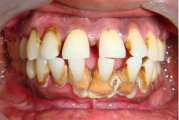

Sümptomid:

- igemed veritsevad (19)

- igemed punetavad (21)

- ige on paistes (mädapunn)

- igemed on tursunud/vohavad (17)

- igemepiir on taandunud (3)

- luu destruktsioon (5)

- vahed hammaste vahel (5)

- halb hingeõhk / suu haiseb (12)